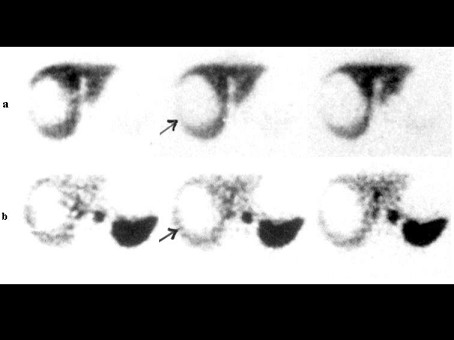

[单选题]一患者的肝胶体显像及肝血池延迟显像如图,诊断是()A.多发肝转移癌B.多发肝囊肿C.多发肝血管瘤D.肝癌并肝内转移E.以上都不是

[单选题]一患者上腹痛,行肝胶体及肝血池延迟6h显像如图,诊断是()A .肝癌B .肝局灶结节性增生C .肝囊肿D .肝硬化E .以上都不是

[单选题]一患者上腹痛,行肝胶体及肝血池延迟6h显像如图,诊断是()。A . 肝癌B . 肝局灶结节性增生C . 肝囊肿D . 肝硬化E . 以上都不是

[单选题]中年男性体检,行肝血池显像早期+延迟显像如图,诊断是()A.肝右后叶血管瘤B.肝左叶血管瘤C.肝多发血管瘤D.正常肝血池显像E.肝右后叶肝癌